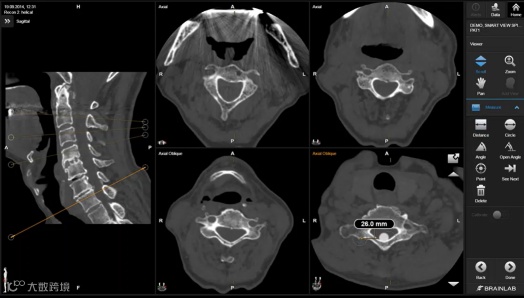

手术规划系统(Elements)

手术规划系统(Elements),是可供全外科使用的术前手术规划系统,具备影像融合、智能分割、智能画笔、智能视图等功能。临床医生能够使用的功能相对简单,面对复杂病例,需要额外的精力进行协调、准备以及患者沟通。而我们的手术规划产品希望能直接赋能临床医生,能够提供全自动的组织分割与重建,多模态的影像融合,手术路径规划模拟,基于混合现实的手术方案讨论与患者沟通,术中数据整合等多方面功能,直接赋能临床医生,为精准化医疗提供更加全面的支撑。